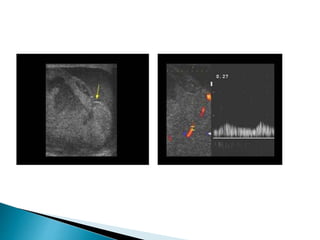

 Doppler ultrasoundwith sensitivity of 85% in the diagnosis of torsion reduced vascularity (absence or poor colour flow, reduced peak systolic velocities) compared with the unaffected side.  Given the importance of operating within a few hours of the onset of symptoms  Neither the performance nor interpretation of an ultrasound examination should delay surgical treatment.  If there is doubt the urologist should operate on clinical grounds

• #59 Incomplete torsion of testis with high resistance to-and-fro flow Spectral Doppler shows high resistance flow in left testis with diastolic reversal, while the right testis shows normal low resistance flow.